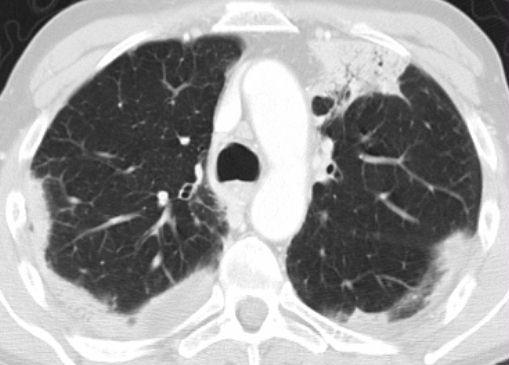

Ví dụ

Các hình ảnh cho thấy hai trường hợp có GGO: một trường hợp không có xơ hóa (có khả năng điều trị được) và một trường hợp có giãn phế quản do co kéo (cho thấy có xơ hóa).

Các hình ảnh mô tả một bệnh nhân với kính mờ (GGO) là dạng tổn thương chủ đạo, kèm theo giãn phế quản do co kéo, gợi ý xơ hóa.

Biểu hiện này phù hợp với một trong những dạng tổn thương có thể gặp của viêm phổi mô kẽ không đặc hiệu (NSIP).

NSIP được đặc trưng về mặt mô học bởi hình thái tương đối đồng nhất của viêm mô kẽ tế bào với các mức độ xơ hóa khác nhau.

Giống như UIP, NSIP chủ yếu ảnh hưởng đến các vùng phụ thuộc trọng lực của thùy dưới nhưng không có xơ hóa lan rộng và tổ ong như trong UIP.

NSIP có thể là vô căn hoặc liên quan đến các bệnh mô liên kết mạch máu hoặc phơi nhiễm với thuốc hay hóa chất.

Bệnh có tiên lượng tương đối tốt, với đa số bệnh nhân đáp ứng với điều trị bằng corticosteroid—khác với UIP vốn có tiên lượng xấu.